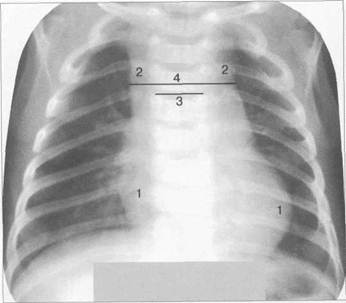

У детей в возрасте до 1 года вилочковая железа имеет наибольшие относительные размеры и массу. Обычно поперечник железы превышает ширину сосудистого пучка сердца, поэтому вер­хняя дуга средостения на рентгенограмме в прямой проекции с обеих сторон представлена ви­лочковой железой. У половины детей обе доли вилочковой железы выступают в сторону легоч­ных полей симметрично. При преобладании размеров одной из долей (чаще правой) верхний отдел средостения расширен асимметрично.

Рис. 9.8. Рентгенограмма грудной клетки в прямой проекции ребенка 2 месяцев.

1 — наружный контур сердца; 2 — наружный контур вилочковой железы; 3 — поперечник грудного позвонка; 4 — поперечник вилочко­вой железы не превышает двух поперечников грудного позвонка.

В возрасте до 1 года железа считается нормальной, если ее поперечный размер на уровне бифуркации трахеи не превыша­ет двух поперечников грудного позвонка (рис. 9.8).